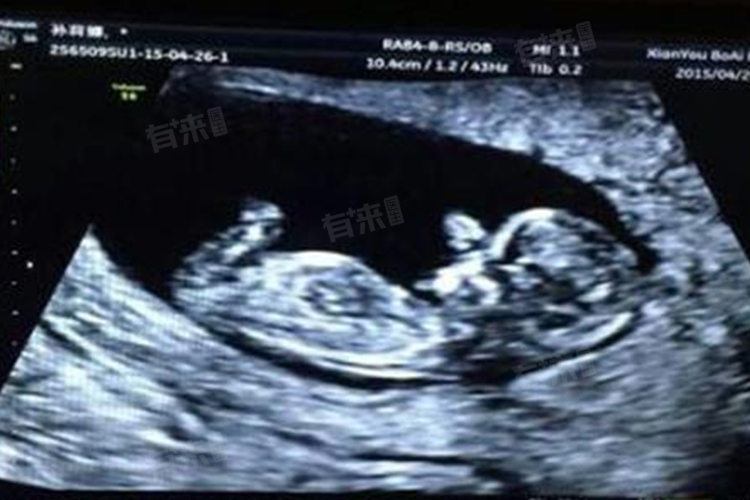

5、系统B超检查:详细检查胎儿各器官系统的发育情况,进行胎儿畸形大筛查。直观了解胎儿在宫内的生长发育情况,及时发现并处理胎儿畸形等问题。